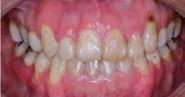

Estudios intraorales, fotografías finales

En la Figura 10 tenemos las líneas medias dentales coincidentes, la corrección de overbite, en la lateral izquierda clase I molar y canina bilateral, una correcta intercuspidación.

La radiografía lateral de cráneo en la Figura 11, se observa un ANB de 2° líneas rojas debido al avance del maxilar, una retroclinación del incisivo inferior a 76° líneas amarillas y mejoría de 1-maxilar a 122° líneas azules.

En la radiografía panorámica se ven 24 órganos dentales (Figura 12) después de realizada la cirugía osteotomía Lefort I maxilar de avance y una mentoplastía; las cuatro placas de fijación con sus respectivos microtornillos en el maxilar líneas de color rojo, la fijación con alambre quirúrgico de acero inoxidable señalados azules.

Para la estabilidad se indicó un retenedor circunferencial superior e inferior con cinturón vestibular (Figura 13).